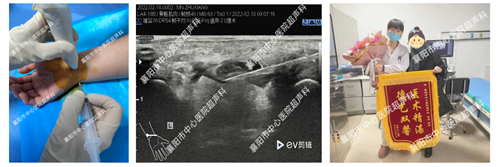

6、超声引导下颈神经根阻滞治疗神经根型颈椎病

7、超声引导下肌肉及软组织内异物定位及取出术

8、腕管综合征的水分离药物注射治疗